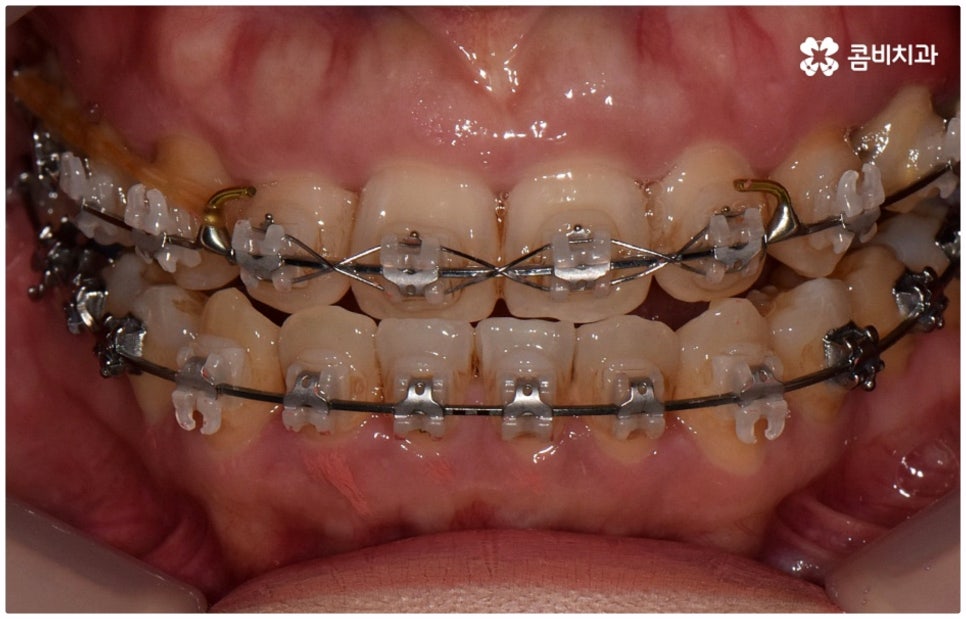

출처 아카이브 열기위아래 치열이 제대로 맞물리지 않으면 음식물을 씹을 때 어려움을 느끼거나 발음상 문제가 생길 수 있습니다. 이것을 부정교합이라고 하며, 그 종류는 상악과 하악의 골격적인 전후방 관계를 기준으로 1급, 2급, 3급으로 나눌 수 있어요. 위아래 어금니는 잘 맞물리는데 치열이 조금씩 삐뚤어져 있거나 치아 사이가 벌어져 있는 등 살짝씩 어긋난 부정교합은 1급, 위 어금니가 더 앞으로 나가있는 부정교합은 2급 (ex. 돌출입), 그리고 아래 어금니가 더 앞으로 나가있는 부정교합은 3급 (ex. 주걱턱) 으로 분류하게 되는데 이 중 오늘 살펴보려고 하는 것은 부정교합 3급에 해당하는 반대교합에 대한 거예요.

정상적인 교합은 윗 앞니가 아래 앞니를 살짝 덮는 정도로 윗니가 조금 더 앞으로 나와 있으면서 위아래 치아가 어금니까지 잘 맞물리는 것을 말하는데 반대교합은 위아래 앞니가 거꾸로 물리는 증상을 보이기 때문에 저작 활동 및 발음 조성이 원활하지 않게 되며 반대교합교정 등 적절한 치료를 받지 않고 방치할 경우 점점 더 주걱턱이 강화되는 쪽으로 뼈가 성장할 수 있어 될 수 있는 대로 빠른 시일 내에 원인을 분명하게 알아보고 그에 맞는 치료를 받는 것이 중요하다고 할 수 있어요.

골격적인 원인이 아니라면 위턱과 아래턱의 위치나 크기에는 이상이 없는데 치아의 맹출 각도 및 방향의 문제로 인해 치아가 반대로 맞물리게 된 치성 반대교합에 해당하는 경우라고 할 수 있는데요. 그 원인으로는 선천적인 치열의 문제 (아래턱 앞니 치축이 앞으로 기울거나 위턱 앞니 치축이 뒤로 들어감), 유치가 너무 빨리 빠지고 영구치가 자리를 제대로 잡지 못해 생긴 문제, 후천적인 습관 (혀를 내밀거나 손톱을 깨무는 등 치열에 좋지 않은 영향을 주는 행위를 지속적으로 반복) 으로 인한 문제 등등을 살펴볼 수 있으며, 보통 이런 경우 앞니 4~6개 치아 일부에 국한된 문제이기 때문에 보다 빠르고 간단하게 교정 치료가 가능하므로 꼭 성장기에 치료를 시작하지 않고 성인이 된 후라고 해도 비교적 쉽게 개선이 될 수 있습니다.

반대교합의 경우 보통 두 원인이 혼재되어 나타나는 경우가 많으며 또한 환자분들의 상황에 따라 정확한 치료가 달라지기 때문에 꼼꼼한 검진 후 각자에 맞는 반대교합교정 치료를 통해 이를 바로잡아 주시길 권유드리고 있어요. 검진과 치료를 받을 때는 3D CT와 같은 정밀 검사 기계를 갖추고 있는 치과에서 임상 경험이 풍부하고 뛰어난 노하우와 기술을 가지고 있는 숙련된 의료진에게 반대교합교정 치료를 진행하는 것이 좋을 거예요.

교정 치료가 생물학적 반응을 이용하는 것이다 보니 성장기에 진행하면 치아 이동 및 회복 속도 등에 장점이 있는 것은 분명하지만 그렇다고 해서 성인 이후 중장년 분들이 교정 치료를 받을 수 없는 것은 아니며 이미 많은 분들이 도움을 받고 계신 만큼 이에 대해서 한 번 고려해 보시면 좋을 거예요. 혹시 성장기 이후로는 양악 수술 등으로만 치료가 가능한 것이 아닐까 생각하셔서 부담스럽게 느끼셨던 분들이라면 지레 겁을 먹고 불편함을 그대로 방치하시기 보다는 검진 및 상담을 통해 적극적으로 이를 해결해 보시길 권유드리고 있어요.

물론 원인과 정도에 따라 외과적인 방법이 필요하신 분들도 있을 수 있지만 교정을 통해 얼마든지 치료가 가능한 경우도 있으며 앞서 말씀드렸던 것처럼 발전된 교정 기술 및 특수 미니스크류 등의 장치 개발을 통해 턱의 방향을 조금씩 회전시켜 원거리 치아 이동을 유발하는 것이 가능해졌기 때문에 예전에는 한계가 있었던 부정교합 케이스도 개선될 여지가 늘어나고 있습니다. 꼼꼼하게 검진을 받으시고 자신의 상황에 맞는 교정 치료를 무리하지 않게 진행하신 후 철저하게 사후 관리를 해주시면 보다 오랜 기간 동안 건강하게 고른 치열을 유지하면서 생활하실 수 있을 거예요.